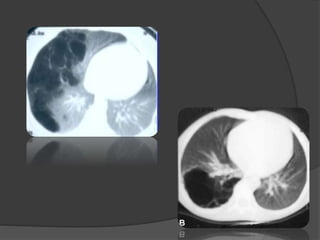

Imagerie

 La radiographie du thorax: Diagnostic (+)

Topographie

 Hyper clarté homogène compressive

 Trame vasculaire conservée mais grêle

 Signes de distension thoracique

 Hernie médiastinale + refoulement

controlatéral

 Pseudo-pneumothorax

 Le scanner thoracique: confirme le diagnostic

Le lobe atteint = hyperclair et hypovascularisé

 Plus sensible:

 Aspect caractéristique des structures vasculaires

étirées et grêles

 Localisation

 Étiologie

 Diagnostic différentiel